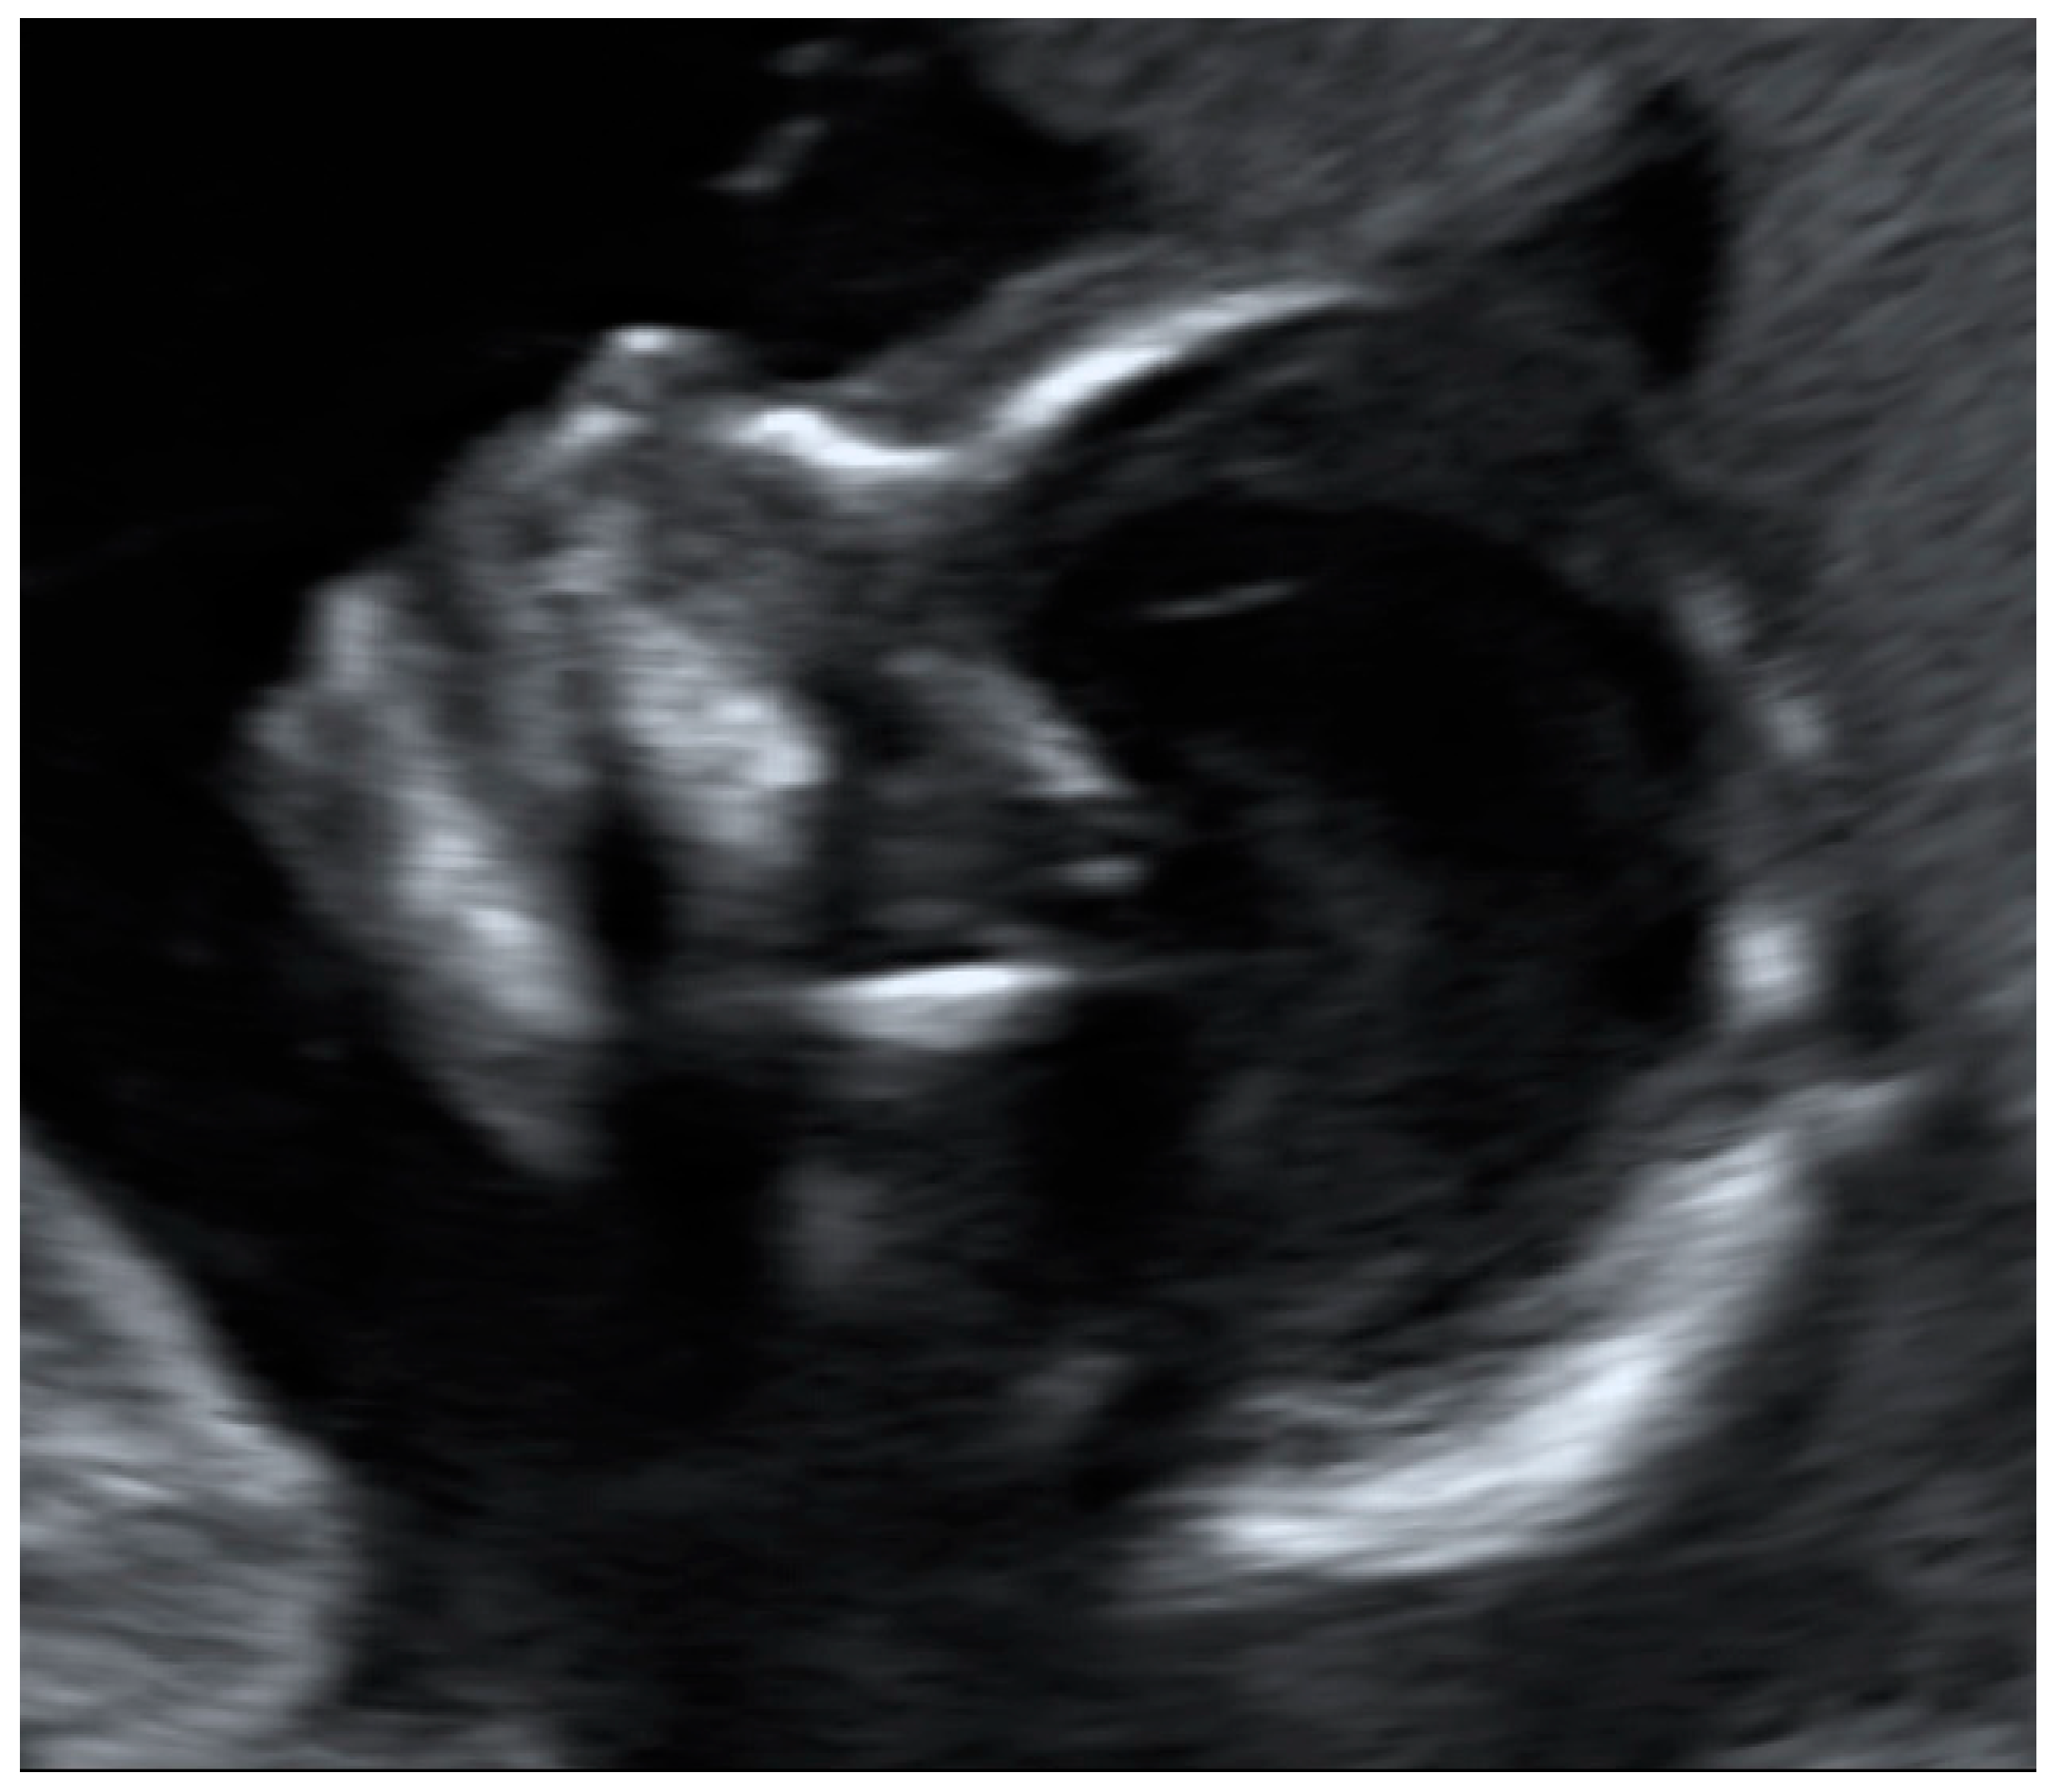

- If the participant was able to show the fetal heartbeat for at least one second during the video sequence lasting 30 s, it was marked as “target located.” For a satisfactory presentation of the fetal profile, the forehead, tip of the nose and chin had to be clearly visible (example in Figure 1). Images and videos taken by the participants in which the fetal profile was also not visible (n = 18) were excluded.

Figure 1. Requirements for satisfactory presentation of fetal profile: the forehead, tip of the nose and chin should be clearly visible. - For a satisfactory presentation of images and videos of the amniotic fluid, hypoechoic areas had to be clearly demarcated from parts of the fetus. The four images and four video sequences representing the amniotic fluid were evaluated separately. If the amniotic fluid was clearly displayed in one quadrant, the respective videos or image sequences were marked as “target located.” It was also examined whether the women were able to display the amniotic fluid in all four quadrants so that retrospective evaluation of a normal amount of amniotic fluid in a participant would be possible. Accordingly, the videos were marked as “4 out of 4 with sufficient quality” only if the amniotic fluid was visible in all four video sequences.